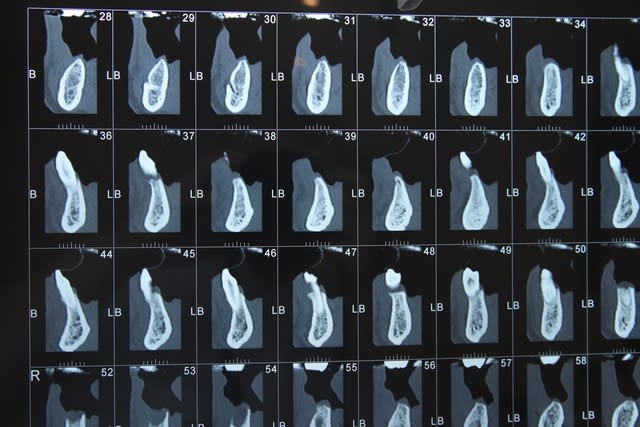

Voici le scan:

Feyimg 8735 c2cykn - Eugenol

Feyimg 8733 kvghzr - Eugenol

Feyimg 8734 fc50c4 - Eugenol

dommage qu'on voit pas ce qu'il y a dans les coupes 50/60...

sinon, c'est une autoroute....là un "all on" 5 ou 6 implants...çà le ferait bien...;-))

Voilà voilà

Feyimg 8742 sgd7sv - Eugenol

je confirme...autoroute...

j'aimerais bien en avoir des comme çà tous les jours à mon cab...;-))

heu...j'ai peut être pas très bien chaussé mes lunettes pxav...mais les repères sous les coupes...si on s'en réfère à la mesure de référence donnée tout à droite de la dernière planche de scan( "règle" de 10cm)...semblent être des repères de plan de coupe de 2mm...

mis à part dans la zone des incisives où là c'est plus étroit (normal)...à partir des canines, on a des crêtes d'au moins 6/8 mm minimun....

peut être que gribouille pourrait confirmer...mais si c'est le cas...je sais pas ce qu'il te faut pour planter....

par contre, d'accord avec toi pour la qualité, ou santé osseuse...il faut peut-être être assez prudent sur ce cas